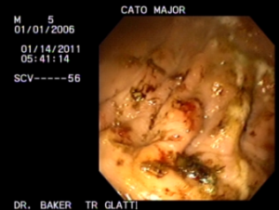

Location: Wonderful Wyoming | This is a from some of the professionals at Total Health, I just received this in an email to better explain GastroPLUS.

What makes T.H.E. unique is that we think outside of the box with all of our products. GastroPLUS specifically works completely differently than other ulcer products. Most ulcer products reduce the acid in the stomach. Even though that is what causes ulcers it is not the main issue at hand. Sometimes when you reduce the acid your horse can get protein entropy or when you take them off the horse over produces the acid and the ulcers come back worse therefore creating a vicious cycle. Our product increases the mucus lining in the horses stomach therefore helping the horse to contain and control the acid. Also our product is a complete supplement therefore it is not just for ulcers. It is also for digestive functioning and has the amino acids, vitamins and minerals your horse would need to stay healthy. My increasing mucus throughout the whole gestational track it enables us to be able to reach the hind gut. GastroPLUS is also go for horses with gestational issues such as diarrhea or a soft stool. It is safe to use long term. Most of the racehorses on our products get GastroPLUS daily at the racetrack.

I also have several scope pictures to show before and afters. pm me emails and I will forward away, just don't be eating a sammich while you look at them  |

Location: Wonderful Wyoming | Here are the graphic pics, I think I can get them on here.

(unnamed.jpg) (unnamed.jpg)

(unnamed (1).jpg) (unnamed (1).jpg)

(unnamed (2).jpg) (unnamed (2).jpg)

(unnamed (3).jpg) (unnamed (3).jpg)

Attachments

----------------

unnamed.jpg (15KB - 475 downloads) unnamed.jpg (15KB - 475 downloads)

unnamed (1).jpg (14KB - 450 downloads) unnamed (1).jpg (14KB - 450 downloads)

unnamed (2).jpg (19KB - 430 downloads) unnamed (2).jpg (19KB - 430 downloads)

unnamed (3).jpg (16KB - 478 downloads) unnamed (3).jpg (16KB - 478 downloads)

|